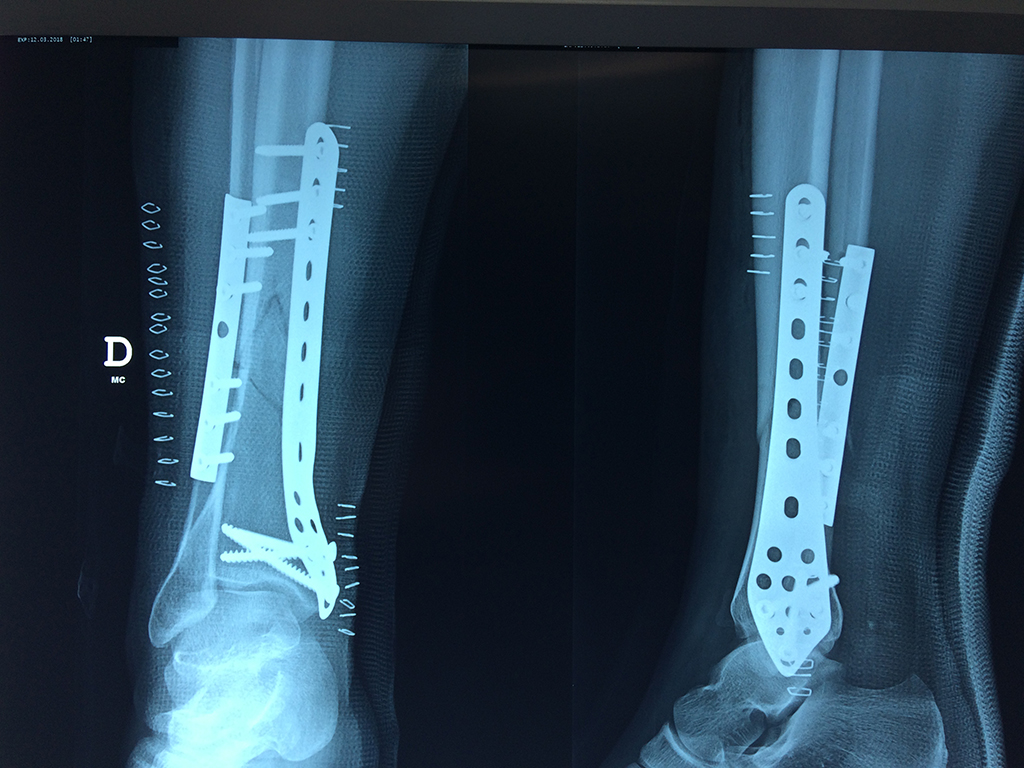

Aunque cada uno de estos huesos puede fracturarse por separado, normalmente la rotura es una lesión que se produce de forma conjunta

La mayor parte de las roturas implican a la parte proximal del hueso (parte del hueso próximo a la rodilla) o a la parte distal (parte del hueso cerca del tobillo).

Debido a la fina cobertura de piel que recubre la tibia y el peroné, las fracturas generalmente son abiertas, es decir, el hueso roto rasga la piel, atravesándola. Las fracturas de tibia y peroné generalmente se producen por un fuerte impacto o torsión.